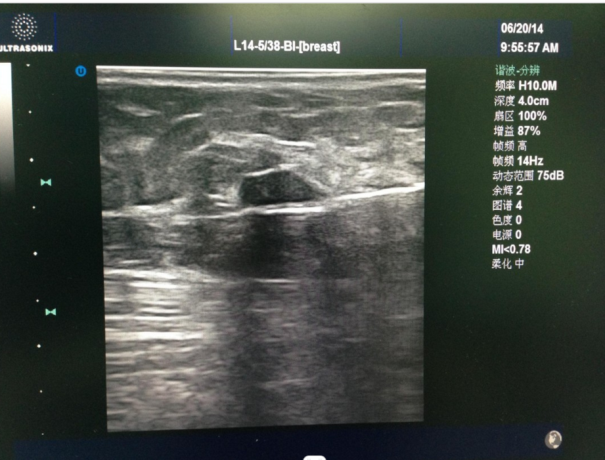

▲彩超引导下穿刺旋切肿块